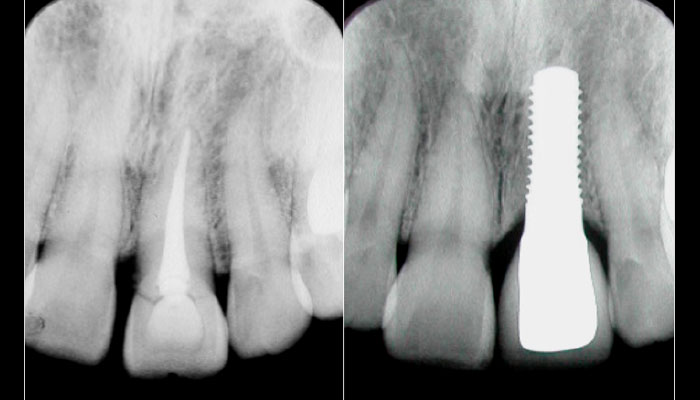

左が治療前、右が治療後のレントゲンです。

向かって右の中切歯がインプラントの歯です。

抜歯から歯が入るまで、3か月半、たった1回の手術で完了しました。

2021年で治療後17年経ちますが、このままの状態で生活されています。 -